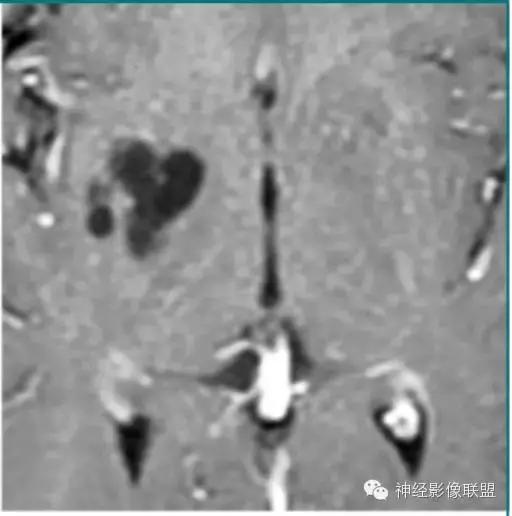

室管膜囊肿